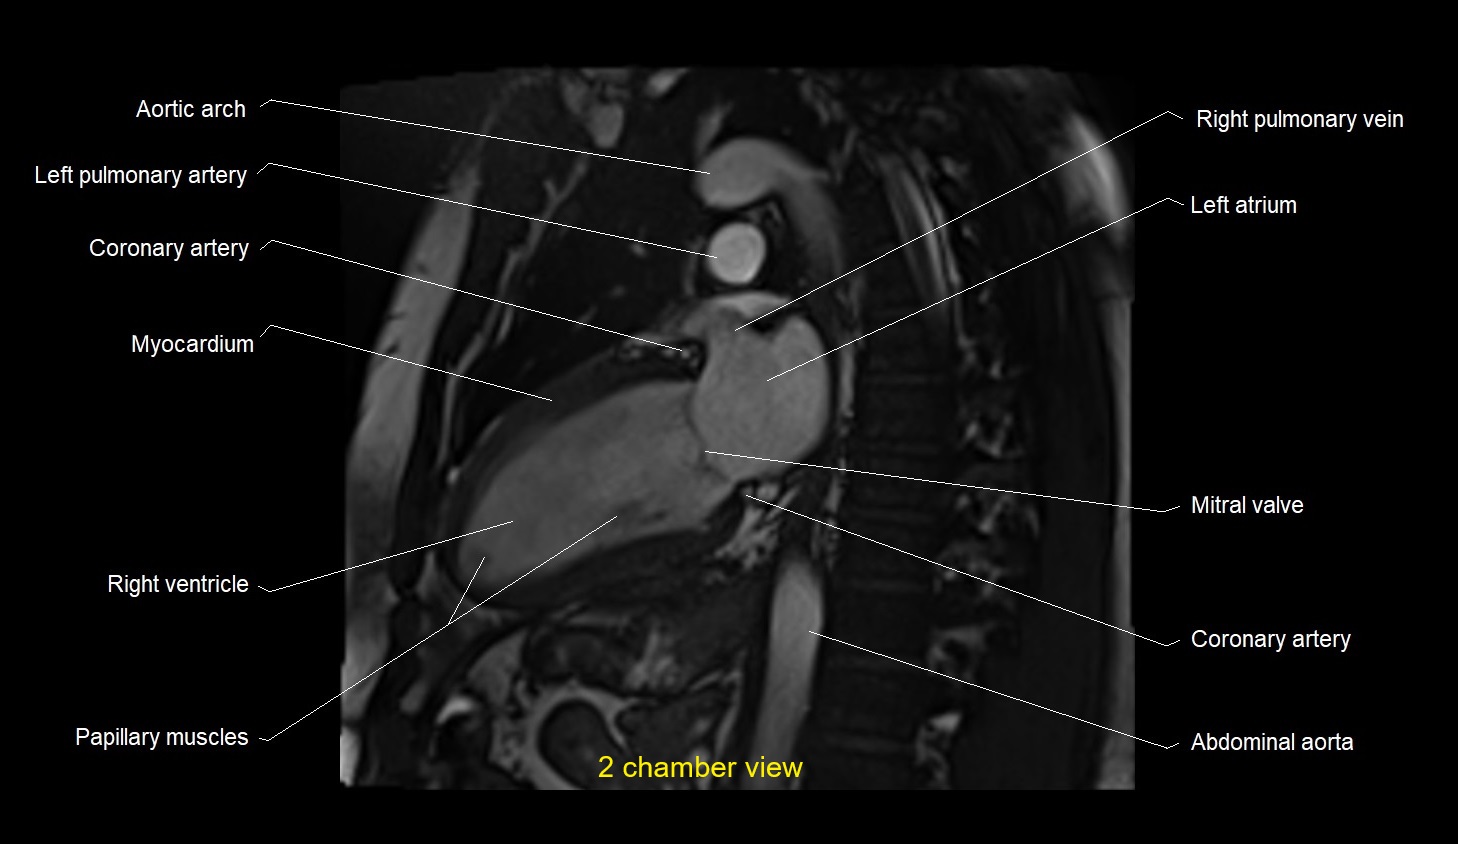

MRI image